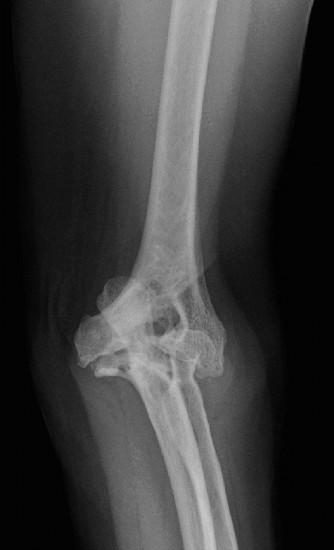

Manage a patient after total shoulder arthroplasty? CASE 18 Dr. Anna Cohen-Rosenblum A 55-year-old female with a history of rheumatoid arthritis diagnosed at age 40 presents to your clinic complaining of 3 years of right shoulder pain acutely worsening over the past week to the point that she is unable to reach for objects from high shelves and needs help getting dressed in the morning. She also notes recent intermittent fevers and severe pain in her left hand and decreased range of motion of the fingers. She participated in a 6-week course of physical therapy last year prescribed by her rheumatologist which provided no relief. She receives an injection of a TNF-alpha inhibitor every 8 weeks. Physical examination reveals

tenderness to palpation, swelling and warmth about the left shoulder with decreased range of motion throughout. Her left hand is neurovascularly intact with ulnar deviation of the fingers and severe limitation of range of motion. Imaging of the right shoulder is shown in Figure 2–52.

Figure 2–52

What is the most appropriate next step in diagnosis/treatment?

The correct answer is (D). In a patient with rheumatoid arthritis, the most likely diagnosis is inflammatory arthropathy involving the shoulder, however, the presence of fevers and acutely worsening pain with swelling and warmth on physical examination necessitates a workup for septic arthritis. MRI of the shoulder (Answer A) might be indicated in the future if there is question about rotator cuff integrity in the setting of a decision to perform a total shoulder arthroplasty, but not at the time of initial diagnosis. Subacromial steroid injection (Answer B) would not be indicated in a patient in whom septic arthritis is suspected. Physical therapy (Answer C) would be helpful for conservative management of inflammatory

The correct answer is (C). It is important in patients with rheumatoid arthritis to address other sources of pain that might impede the postoperative rehabilitation process. This patient will be unable to use her right, dominant hand as effectively after shoulder surgery, and will be far more reliant on her left hand in the postoperative period. Since she has severe pain and deformity of the left hand, she should be evaluated by a hand surgeon to determine whether this issue might be addressed prior to her undergoing an operation on her shoulder. Choice A is incorrect not only because the left hand should be evaluated first, but because imaging of her right shoulder reveals severe erosion as well as osteopenia of the glenoid, which is a contraindication to total shoulder arthroplasty due to placement of the glenoid component. Choice B is incorrect only because of the timing with this patient; it is actually the most appropriate operative choice given her poor glenoid bone stock and relatively younger age. Choice D is incorrect as arthrodesis is more appropriate for patients with failed total shoulder arthroplasty, and end-stage rheumatoid arthritis (arthritis mutilans) complicated by septic arthritis.